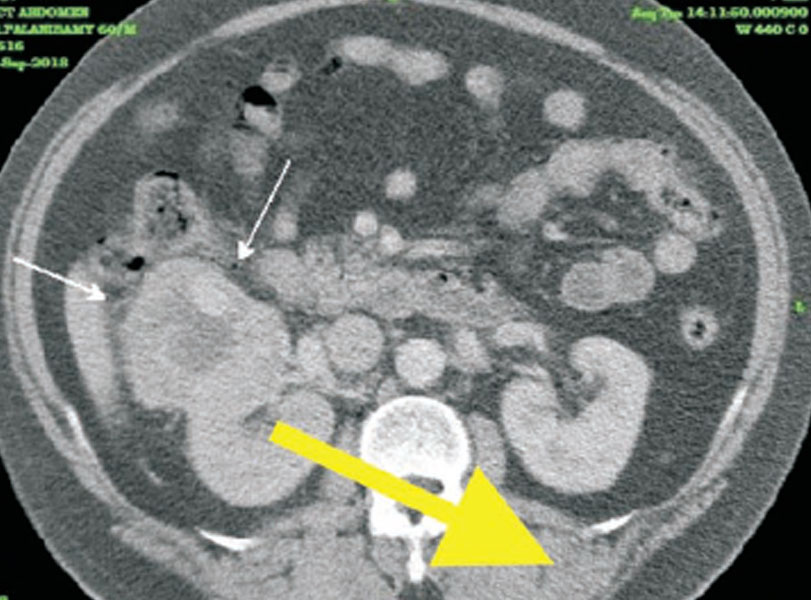

65 வயது ஆணுக்கு கிட் ஸ்கேன் பரிசோதனையில் வலது சிறுநீரகத்தில் புற்றுநோய் கட்டி கண்டறியப்பட்டு லேப்ரோஸ்கோபி சிகிச்சை மூலம் அகற்றப்பட்டது. திசு பரிசோதனை அறிக்கை Multifocal Clear Cell Carcinoma .